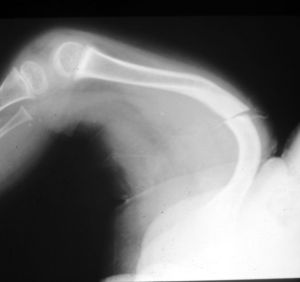

玻璃娃娃 (成骨不全症),一般人稱為「玻璃娃娃」,或「唐瓷娃娃」。指的是一種因先天遺傳性缺陷,而引起「第一型膠原纖維」病變造成骨骼強度耐受力變差,而容易脆弱骨折的疾病。此種疾病發生率並不高,據歐美國家統計,二萬個寶寶之中,大概只會出現一個病歷,比例約為二萬分之一。